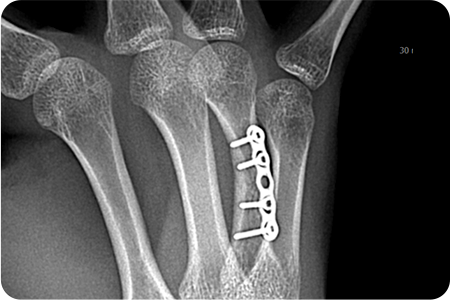

X-ray 및 CT를 통해 골절 형태와 전위 정도를 확인합니다.

골절된 뼈를 원래 위치로 맞추는 정복 작업을 진행합니다.

금속판, 나사, 고정막을 이용해 뼈를 고정합니다.

손은 작은 뼈들이 정교하게 연결되어 있어

골절 시 기능 손상이 크기 때문에,

정확한 정복과 고정이 중요합니다.

골절·외상 수술은 손상된 뼈와 조직을 정밀하게 맞추고 금속판·나사·핀 등을 이용해 안정적으로 고정하는 치료입니다.

이 과정에서 뼈의 정렬과 관절 기능을 회복하기 위한 섬세한 판단이 필요하기 때문에,